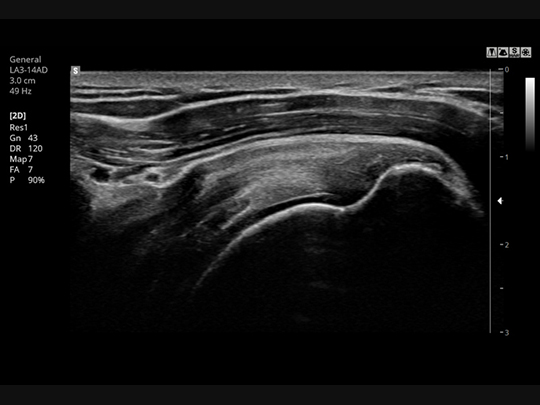

Linear array transducers

LA3-14AD

- Application: abdomen, musculoskeletal, small parts, vascular

S-Vision™ Imaging Engine

S-Vision™ imaging engine effectively removes noise artifacts resulting in clear, detailed resolution and tissue uniformity.

S-Harmonic™

This new harmonic technology provides greater image uniformity from near to far field while reducing signal noise.